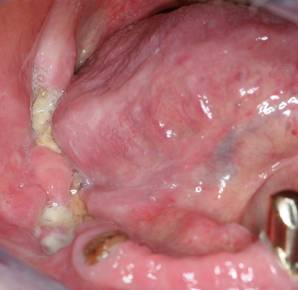

Unter Knochennekrose (Osteonekrose) versteht man eine Erkrankung, bei der Teile eines Knochens oder der gesamte Knochen absterben. Im Kopf- und Halsbereich sind Ober- und Unterkiefer hiervon am häufigsten betroffen. Bis vor wenigen Jahren war die häufigste Ursache für das Absterben von Kieferknochen eine vorausgegangene Bestrahlung im Kieferbereich. Die abgestorbenen Knochenareale wurden als Osteoradionekrose bezeichnet. Durch die in den letzten Jahren zunehmend breite Anwendung von Bisphosphonaten bei der Therapie von Knochenmetastasen (z.B. als Folge von Brust- oder Prostatakarzinomen) und bei der Osteoporosetherapie haben diese Medikamente heute die größte Bedeutung für die Entstehung von Kiefernekrosen. Dieses Krankheitsbild, welches der Osteoradionekrose stark ähnelt, wird Bisphosphonat-assoziierte Osteonekrose oder BONJ (bisphosphonate-associated osteonecrosis of the jaw) genannt. Auch die kürzlich für die Krebstherapie zugelassenen Antikörper Denosumab und Bevacizumab können zur Osteonekrose von Kieferanteilen führen. Eine Kiefernekrose zeichnet sich unter anderem aus durch freiliegenden, nicht von Schleimhaut bedeckten Kieferknochen, zunehmende, scheinbar grundlose Zahnlockerungen, Eiteraustritt aus dem Kiefer oder auch durch Kieferbrüche ohne erkennbare äußere Einwirkung oder Ursache.

Knochennekrosen des Ober- und Unterkiefers treten gerne als Nebenwirkung bei der Einnahme von Medikamenten gegen Knochenstoffwechselstörungen (Osteoporose) und Tumoren (z.B. bösartige Tumoren der Brustdrüse und der Prostata) auf. Während diese Nebenwirkung früher nur den Bisphosphonaten (Diphos®, Didronel®, Etidronat 200®, Bonefos®, Ostac®, Skelid®, Aredia®, Fosamax®, Bondranat®, Actonel®) zugerechnet wurde, zeigen sich inzwischen ähnliche Kiefernekrosen auch unter oder nach Therapie mit Prolia® und XGEVA® (Denosumab, RANKL-Antikörper) sowie Avastin® (Bevacizumab, VEGF-Antikörper). Im Englischen  wird daher auch von MRONJ (medication-related osteonecrosis of the jaw) gesprochen. Gelangen zusätzlich zur Einnahme dieser Medikamente Bakterien ins Knochengewebe (z.B. durch von den Zähnen ausgehende Infektionen, Prothesendruckstellen oder zahnärztliche Eingriffe), können sich diese im geschädigten Knochen schnell ausbreiten und ausgedehnte Entzündungen verursachen. Begünstigend wirken eine dünne Schleimhautbedeckung und eine geringe Durchblutung. So ist der Unterkiefer doppelt so häufig wie der gefäßreichere Oberkiefer betroffen. Die Wahrscheinlichkeit dieser Medikamentennebenwirkung steigt mit zunehmender Behandlungsdauer, steigender Medikamentendosis und ist zusätzlich vom Medikament selbst abhängig. Hochwirksame, moderne Bisphosphonate (sog. Amino-Bisphosphonate) oder die i.v.-Medikamentengabe (im Gegensatz zur Tabletten-Einnahme) haben ein höheres Risikoprofil. Weitere Risikofaktoren sind hohes Alter, Nikotinkonsum und eine schlechte Mundhygiene. Da die Medikamentengabe aufgrund der ursächlichen Grunderkrankung häufig nicht pausiert werden kann und die Wirkung der Medikamente sehr lange anhält (oft viele Monate bis Jahre), sollten  unter laufender Therapie mit diesen Substanzen zahnärztliche und insbesondere zahnärztlich-chirurgische Eingriffe nur unter antibiotischem Schutz erfolgen und eine plastische Deckung des Kieferknochens mit Schleimhaut zwingend beinhalten. Um eine spätere Verschleppung von Bakterien in den geschwächten Knochen zu verhindern, sollten prophylaktisch vor der Einleitung einer Therapie mit Bishosphonaten oder den o.g. Antikörpern alle potentiellen Infektionsherde im Kiefer fachmännisch beseitigt werden.

Ist es, egal durch welche der o.g. Ursachen, zu einer sichtbaren Kiefernekrose gekommen, so sind, je nach Schweregrad bzw. Ausprägung verschiedene therapeutische Schritte notwendig, um eine weitere Ausbreitung der Nekrose und zunehmende Schmerzen, aber auch eine drohende Kauunfähigkeit zu verhindern. In den meisten Fällen ist eine alleinige antibiotische Therapie und lokale Wundpflege mit antibakteriellen Mundspüllösungen nicht ausreichend, da der betroffene Kieferabschnitt nicht mehr zur Regeneration fähig ist. Der abgestorbene Knochenanteil muss vielmehr chirurgisch abgetragen und der darunter liegende, noch gesunde, blutende Kieferabschnitt sicher mit Schleimhaut bedeckt werden. Zudem erhalten Patienten symptomorientiert eine Schmerztherapie. Zusätzlich kann eine hyperbare Sauerstofftherapie, wie sie zur Steigerung des Sauerstoffangebots im Gewebe angewendet wird, ergänzend angewendet werden. Trotzdem bleibt der weitere Krankheitsverlauf nicht selten ungewiss. Bei schwereren Verläufen oder bei nicht seltenem, nach wenigen Wochen oder Monaten Wiederaufflammen der Nekrose muss weiter chirurgisch interveniert werden. Abgekapselte nekrotische Areale (sog. Sequester) müssen entfernt werden. Umfasst die Nekrose die gesamte vertikale Ausdehnung des Unterkiefers, muss gegebenenfalls ein kompletter Kieferabschnitt entfernt werden (sog. Kontinuitätsresektion). Die Kontinuität des Kiefers wird in solchen Fällen zunächst durch Platten und Schrauben vorübergehend wieder hergestellt. Kommt es nach dieser chirurgischen Maßnahme zu keinem Wiederaufflammen der Nekrose im Randbereich der Kieferstümpfe, kann nach wenigen Wochen eine knöcherne Rekonstruktion erwogen werden (z.B. durch Verpflanzung von körpereigenem Knochen aus dem Becken, dem Wadenbein oder dem Schulterblatt).